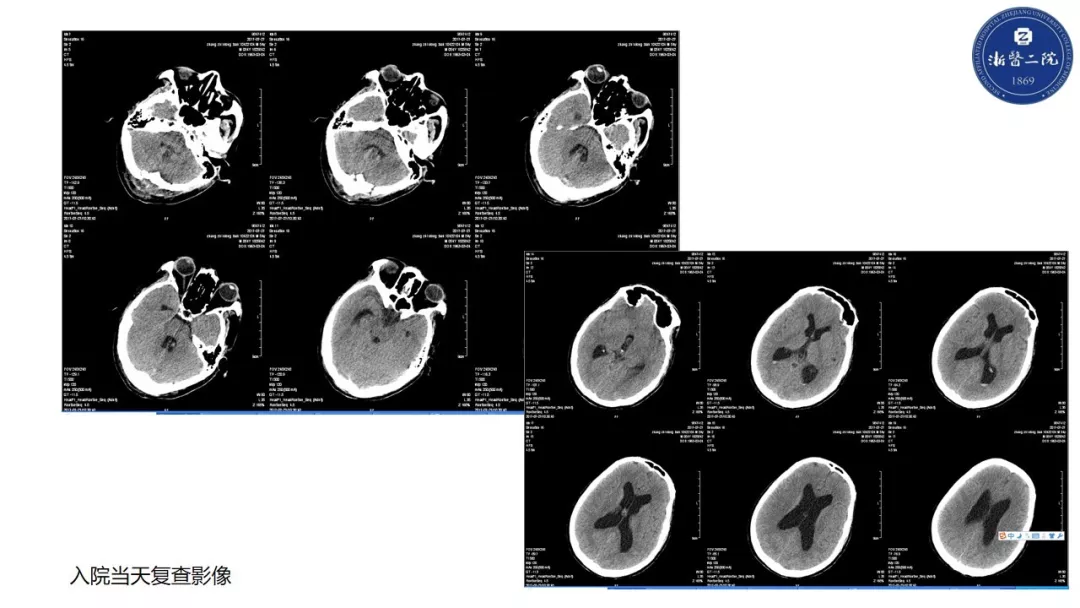

精彩点评 一、54岁男性,主要诊断:四脑室占位伴有幕上脑积水。术后病理诊断:颅内血管母细胞瘤。病人术后第四天,出现体温超过38.5度。 二、从诊断的思路上来讲,对于这种围手术期的病人。术后的体温升高,尤其是异常升高,首先,要考虑手术相关的颅内感染;其次,要考虑肺部感染的可能(因为病人术前就有右下肺的纹理增粗且有临床症状);再次考虑泌尿系感染的可能。下丘脑反应不应该考虑是此患者发热的原因之一。 三、可喜的是病人经过多学科协作积极治疗后,预后良好。尤其是在出现第6天出现意识变化后,经过气管插管及后期的气管切开等一系列积极的气道管理及重症管理,逆转了病情进展,而且术后脑脊液的循环通路完全通畅,没有梗阻性脑积水和炎症继发的交通性脑积水。第二,颅内感染经过后期的积极治疗,病人也达到临床治愈,但是,后期的脑脊液化验资料相对不全。 四、针对后颅窝操作围手术期感染的预防有如下建议: 1. 水密缝合硬膜以及手术后的伤口加压包扎是基本原则,此患者术前诊断为梗阻性脑积水。手术过程中如能提前放置脑室外引流,那么对手术以后的引流以及脑积液性状的观察均会有帮助,且防止术后出现颅内压增高; 2. 其次,病人有体温变化的时候,首先要查看伤口,并进行腰穿。化验脑脊液并送检细菌培养。这是一个基本的步骤,然后再进行经验性的用药,目前来讲脑脊液涂片的阳性率并不高,资料认为大概在5%-30%(北京协和医院资料大约为8%)。因此即使涂片阴性,也不能排除颅内感染的诊断。要综合考虑颅内感染的临床诊断; 3. 一旦诊断为是颅内革兰氏阳性菌感染,要进行经验性抗生素的调整,万古霉素、去甲万古霉素、利奈唑胺,均是有效药物,药物敏感性都非常好,要根据医院的流行病学情况、病人的个体差异,选择使用。 4. 要高度重视后颅窝手术后的气道管理,防止出现二氧化碳储留以及因吞咽障碍导致的误吸和肺炎。 魏俊吉 教授 北京协和医院神经外科副主任 北京协和医院神经急重症专业组组长 中国神经外科重症管理协作组副组长兼秘书长